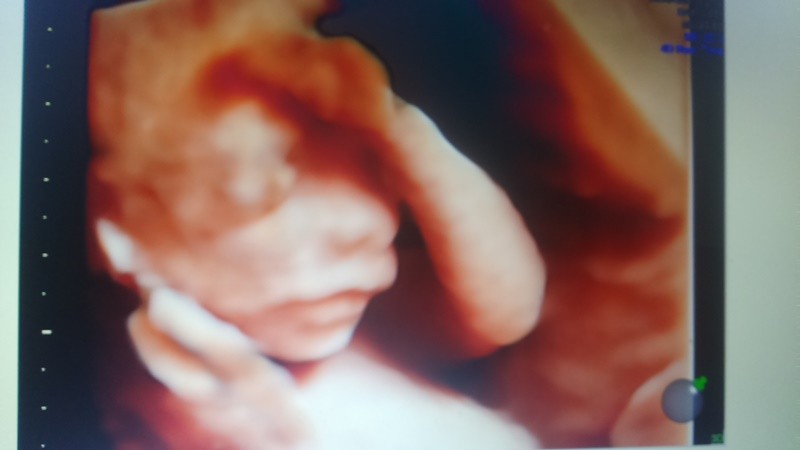

Ja dzis tez bylam na badaniu. Z Usg skonczylam 19tyg, Mlody spory, wazy jak blisko cukier

950g i wciaz sie nie chce przekrecic czyli od poczatku wbil dupsko w moja dziurke i tak siedzi posladkowo przez co kopie nisko po pecherzu. Szyjka ponoc ok 3,5 wiec nie wiem kto jak mierzyl. Fotki brak ale jak widxialam jak wyglada to co do karty przypinal hmm to nasuwaja sie slowa... NFZ! ;-)